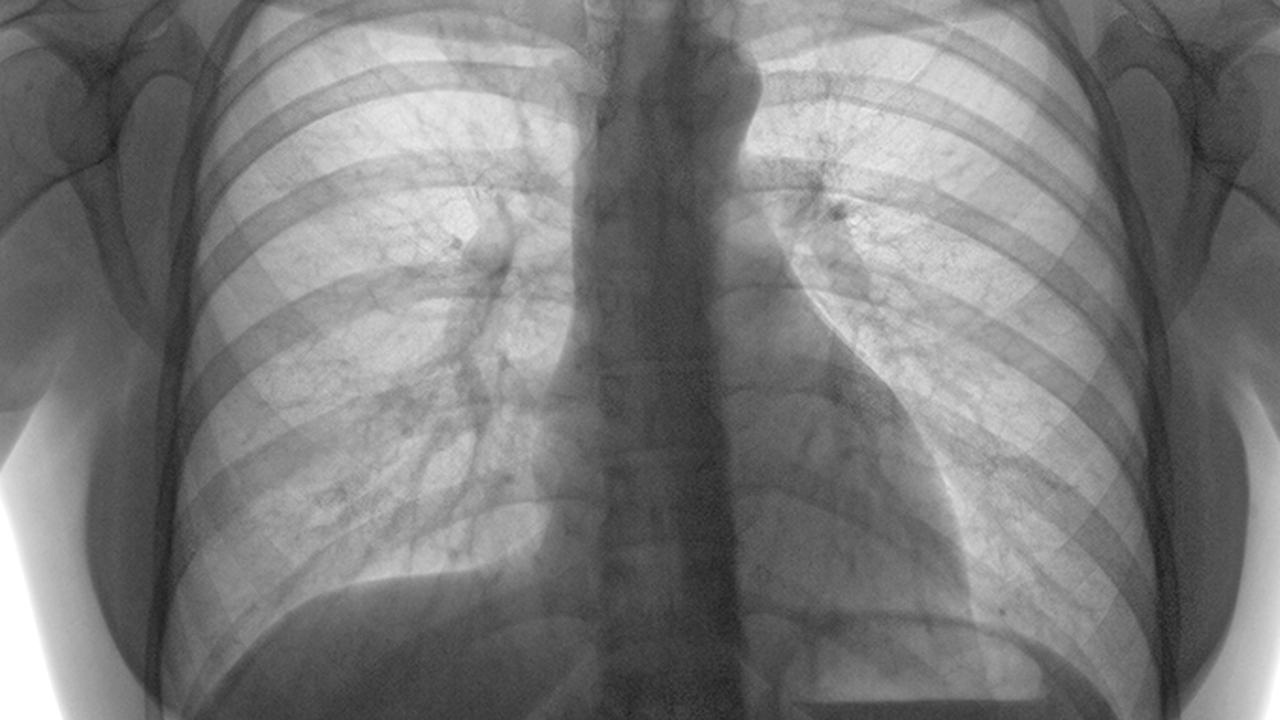

肺结节是一种常见的肺部病变,其发病原因多样,包括感染、炎症、肿瘤等。早期发现和准确诊断对预后至关重要,因此选择专业医院进行规范诊疗十分必要。